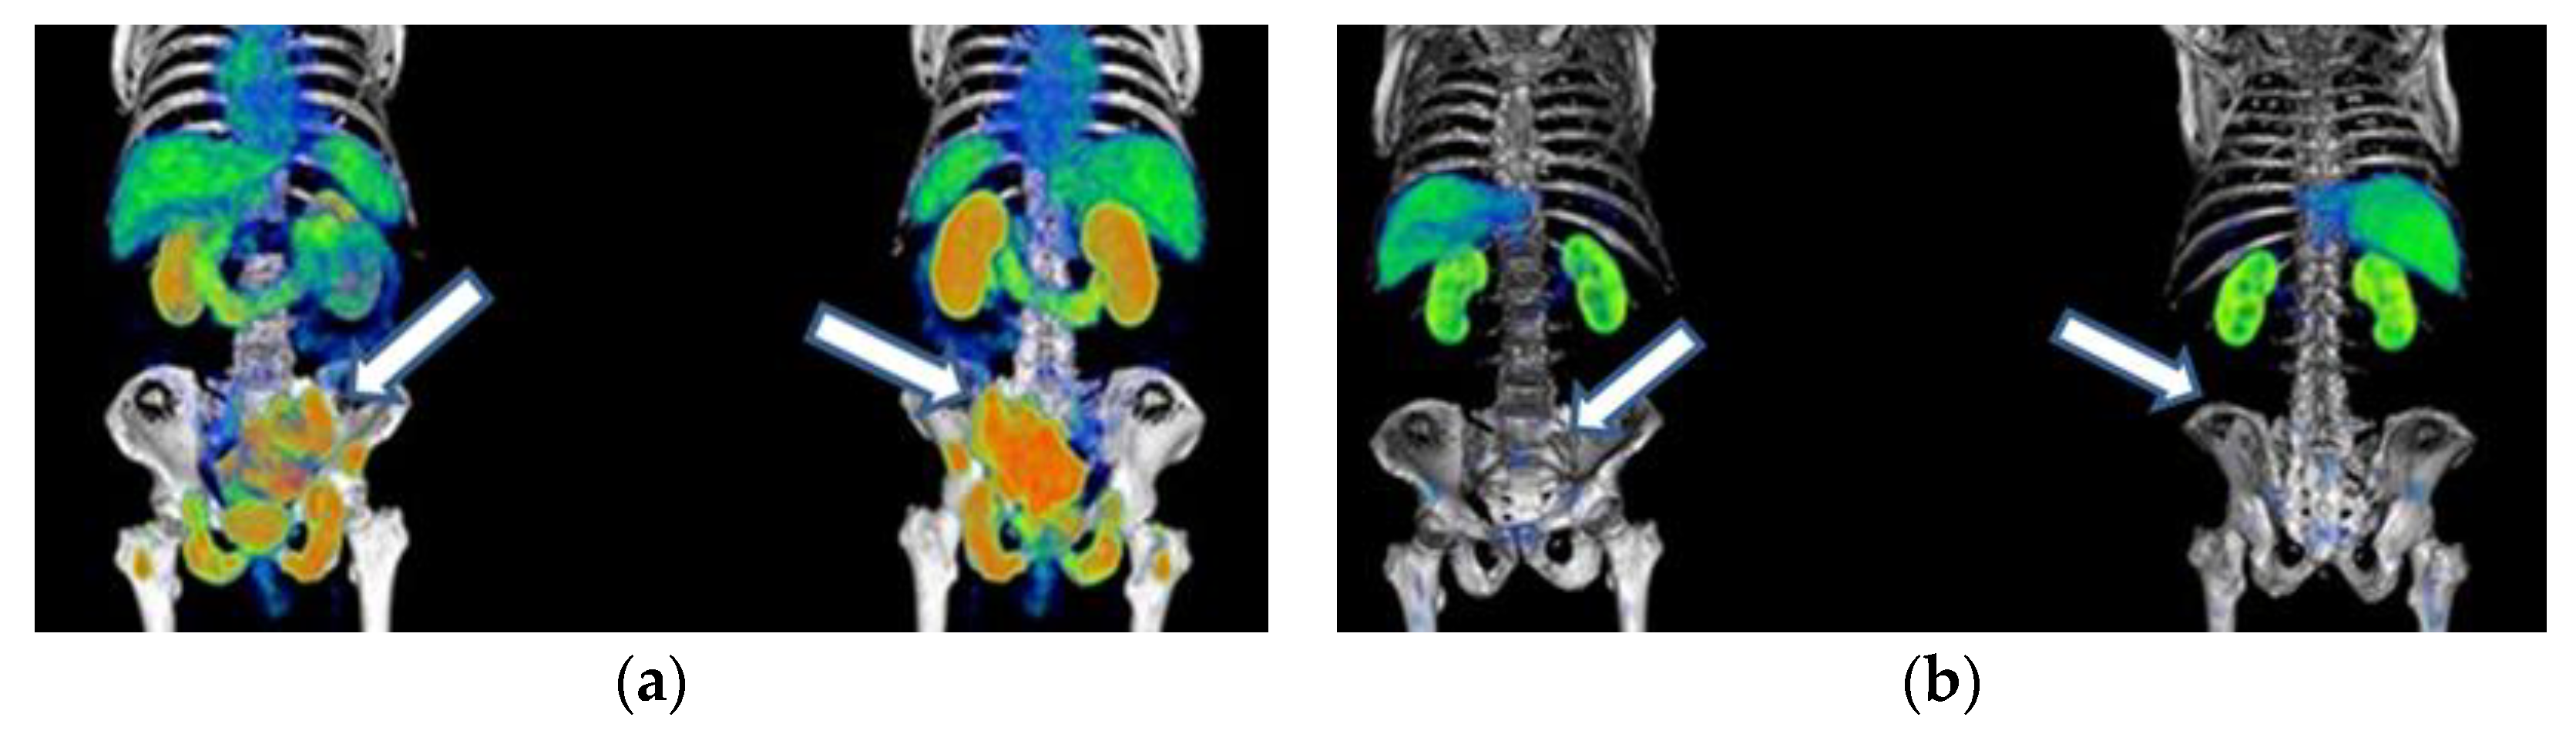

Figure A1. Patient with mCRPC who had a partial response to 177Lu-iPSMA treatment: (a) anterior and posterior 68Ga-iPSMA imaging before 177Lu-iPSMA treatment, and (b) after 177Lu-iPSMA therapy (four doses of 7.4 GBq). Arrows indicate tumor lesion sites.

177Lu-iPSMA therapy is a convenient option for the treatment of multiple metastases and large tumor lesions (Appendix A) (Figure A1, Figure A2 and Figure A3). For example, in the case shown in Figure A1, the patient suffered from severe pain characteristic of the terminal stage of the disease. However, two weeks after administration of the first dose of 177Lu-iPSMA, the subject showed relevant pain relief. Furthermore, after administering four doses of 177Lu-iPSMA (four doses of 7.4 GBq), metastatic lesions in the hip and spine were significantly reduced, prolonging the patient’s life for 19 months after therapy. In this context and based on the results of this study, 177Lu-iPSMA therapy should be considered and evaluated in future clinical trials as a second-line rather than third- or fourth-line therapy in patients with mCRPC, with the potential to improve patient survival.